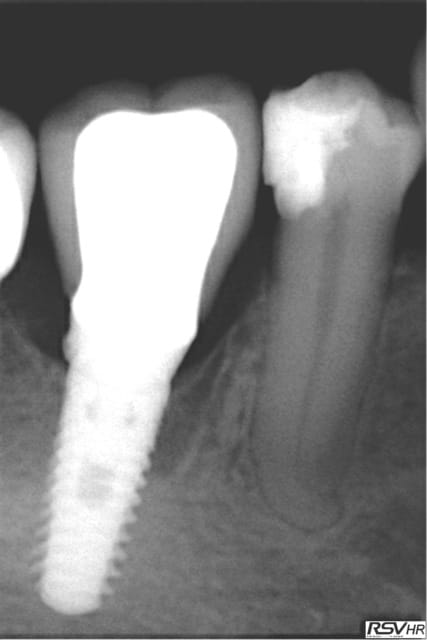

même si je me redirige plutôt vers Zimmer avec une insertion primaire supérieur (à mon avis ) voici un cas de plusieurs années

j'avais gardé une racine distale de 46 (montage 2 ccm soudées au début 4647- avec diastème avec 45 ;2008;le montage

n'a pas tenu longtemps=extraction racine distale et

implantation immédiate legacy2 7 mm(2011)

et ccm transvissée 3 mois après

radio à 2015